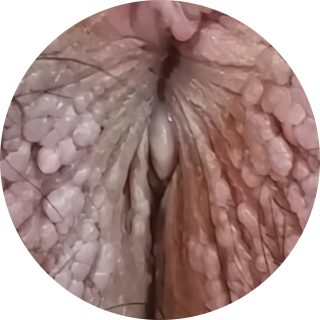

무증상인 경우도 많습니다. 여러 개가 다발로 생기고,

닭벼슬이나 양배추처럼 보기 불편한 모양을 띠기도 합니다.

양배추모양 (닭벼슬)

양배추모양 (닭벼슬) 작은 구진모양

작은 구진모양 물집 형태

물집 형태 편평사마귀

편평사마귀

내부로 퍼질 경우 내시경 검사가 필요합니다.

특히 요도 곤지름은 혈뇨, 두 갈래 소변 등 증상이 없거나 미세해

놓치기 쉬운 만큼 정확한 진단이 중요합니다.